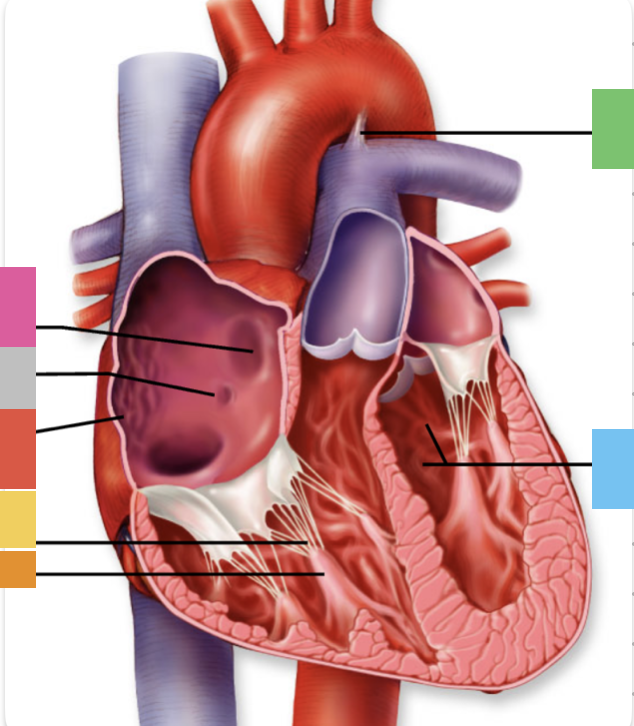

light purple

base

purple

apex

grey

right atrium

pink

right auricle

green

left atrium

green

left auricle

blue

right ventricle

orange

left ventricle

green

coronary (atrioventricular) sulcus

pink

interatrial septum

dark blue

interventricular septum

green

anterior interventricular sulcus

green

posterior interventricular sulcus

orange

aortic valve

yellow

pulmonary valve

red

tricuspid valve (right AV)

purple

bicuspid valve (left AV)

yellow

chordae tendineae

orange

papillary m.

blue

trabeculae carneae - only in ventricles

red

pectinate m. - only in R atrium

pink

fossa ovalis

grey

opening of coronary sinus